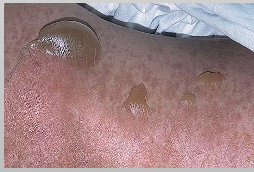

What is acantholysis in Pemphigus Vulgaris?

Epithelial cell separation “INTRA-EPITHELIAL”

What is Nikolsky sign in Pemphigus Vulgaris?

Gentle finger pressure with movement on clinically normal mucosa can produce acleavage in the epithelium and result in the formation of a bulla

What are Tzank cells in Pemphigus Vulgaris?

Loss of attachment between the epithelial cells results in detached cells that appear rounded, present in the area of separation

Sloughing of the epithelium Ulcers in Pemphigus Vulgaris

What is the diagnosis for Pemphigus Vulgaris?

Biopsy and Direct immunofluorescence (DIF)- INTRA-EPITHELIAL separation

What is the treatment for Pemphigus Vulgaris?